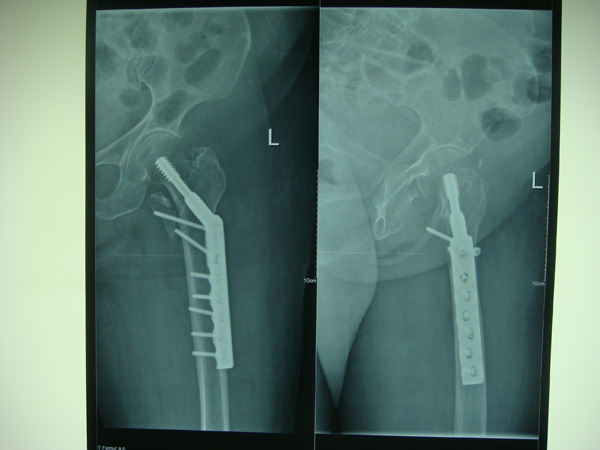

7月9日,莆田盛興醫(yī)院為一名89歲的女性髖部骨折患者順利實施了手術(shù)。

數(shù)日前,東莊鎮(zhèn)89歲的林阿婆外出時腳底不慎打滑,摔倒在地,臀部著地后頓時疼痛難忍,家人立即將她送往莆田盛興醫(yī)院骨科治療。拍片提示:右股骨粗隆間骨折??紤]到由于老人年齡大、體質(zhì)差,又曾患過腦梗,骨折處如果進(jìn)行手術(shù)復(fù)位鳳險很大。為了提高生活質(zhì)量,在征得患者及家屬同意,經(jīng)骨科、內(nèi)科、麻醉科共同會診及術(shù)前相關(guān)準(zhǔn)備后,于7月9日骨科主任陳長光副主任醫(yī)師主刀下行“切開復(fù)位DHS內(nèi)固定術(shù)”, 手術(shù)順利完成,術(shù)中出血量少,各項生命體征平穩(wěn)。術(shù)后指導(dǎo)其肢體功能鍛煉,患者病情恢復(fù)良好,現(xiàn)已能下地行走活動,生活質(zhì)量得到明顯提高。

股骨骨折是老人容易發(fā)生的常見損傷,由于老年人體質(zhì)較弱,手術(shù)耐受力差,許多人股骨骨折后選擇保守治療,造成長期臥床,身心極為痛苦,也給親屬造成極大負(fù)擔(dān)。此次莆田盛興醫(yī)院為89歲老人實施股骨手術(shù)成功,給高齡股骨骨折老人康覆帶來了福音。